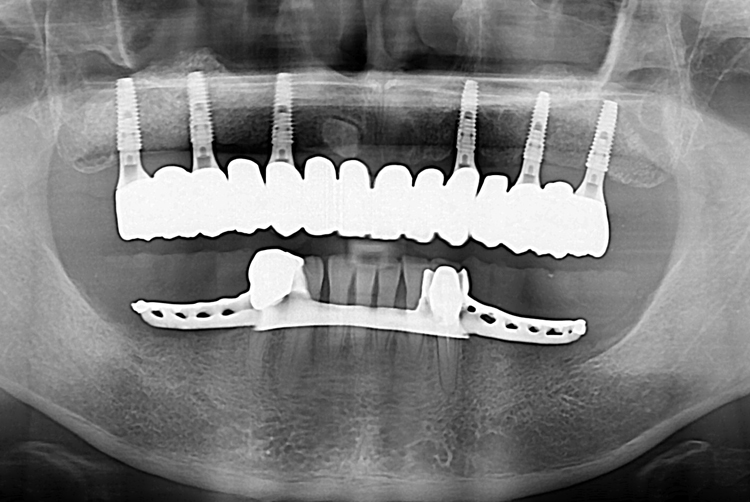

[임플란트] 전체 임플란트

치료전 : 2019-08-02

치료후 : 2019-11-20

세종치과는 많은 환자와 다양한 케이스를 바탕으로

항상 편안한 임플란트 수술을 제공하고자 노력하고,

오래동안 튼튼히 쓸 수 있는 임플란트 수술을 가장 큰 목표로 삼고 있습니다.